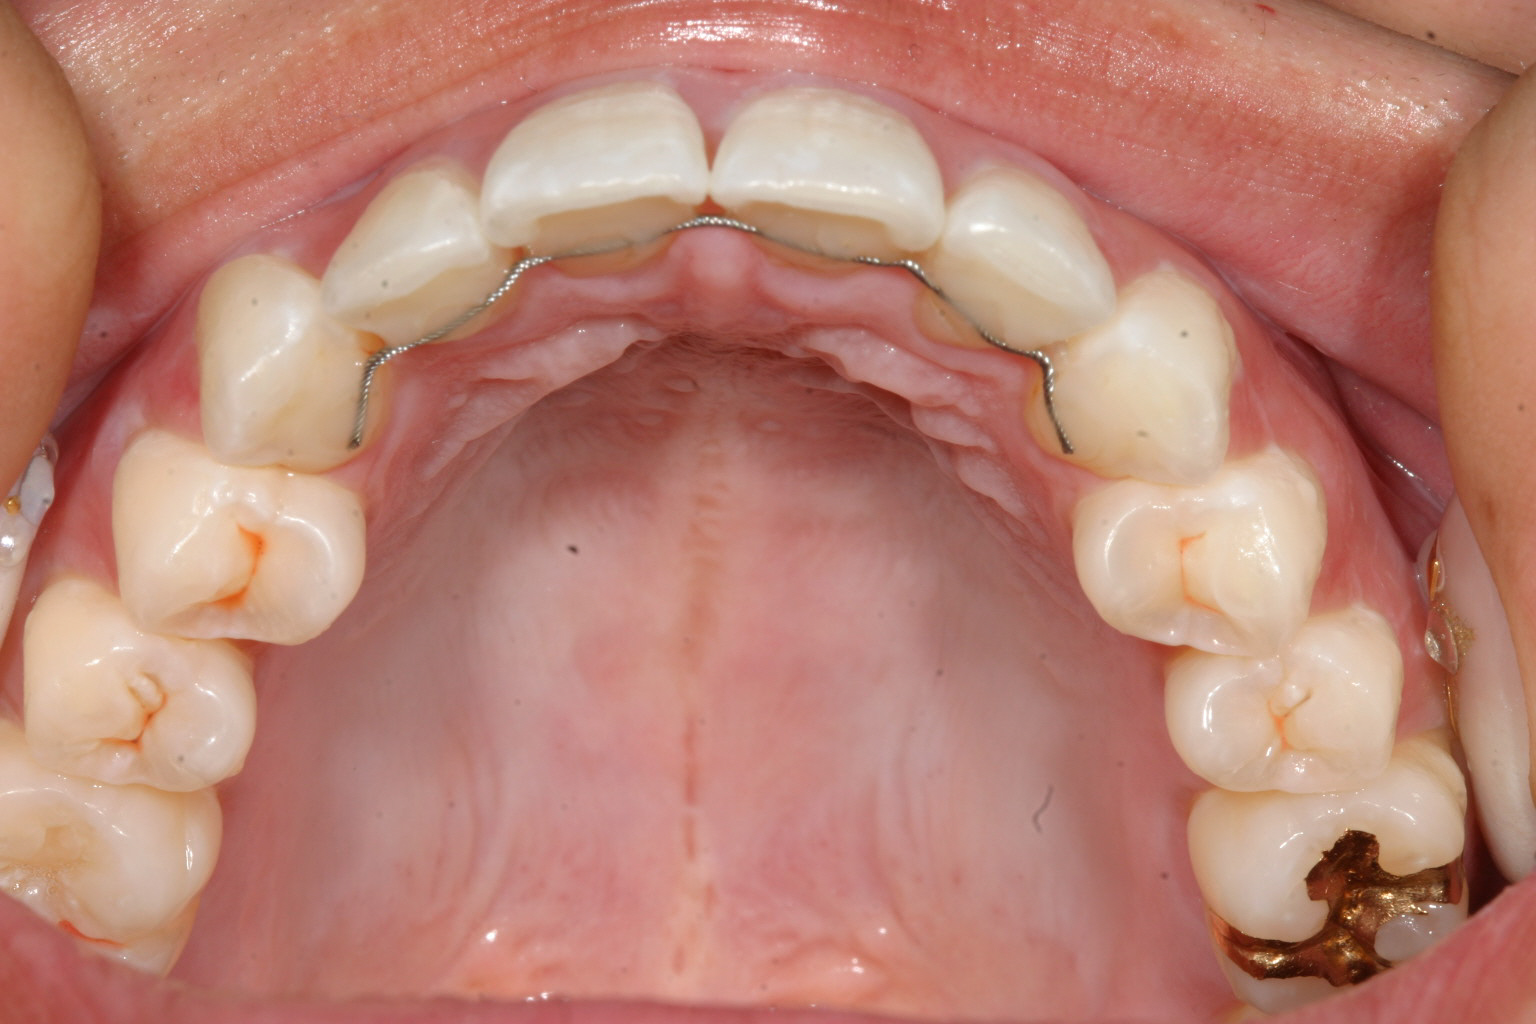

インプラントとワイヤーとバネの力を利用して右側臼歯を遠心移動してるのが分ります。

上にインプラントとワイヤーとバネです。 下はマルチループです。

写真上部にインプラントが見えます。

特に難儀したのが右上の奥歯の位置関係が悪く、先ずは右上の親知らずを抜歯してそこに奥歯を順番に後ろへ送っていくと言う手順です。そう言うふうにする事により飛び出した犬歯をアーチに乗せると言う事が可能になりますが手間のかかる仕事でした。